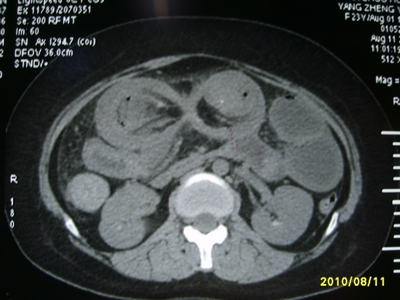

5天前突发腹痛剧烈难忍,伴解淡血水样便。近一天来腹痛缓解,没有明显的腹膜炎的体征。今天照的腹部ct。从ct上看感觉是一个绞窄性肠梗阻,但是现在没有腹痛。不好解释

要有麻烦了,感觉小肠有套叠还有扭转改变,估计部分已有坏死。

高位肠梗阻(不全性),原因小肠(空肠)扭转,肠壁水肿增厚,成年人肠梗阻要排除合并占位,建议手术。

绞窄性肠梗阻_肠管套叠 扭转,肠壁明显水肿。

支持绞窄性肠梗阻,肠壁明显水肿并见有多发小泡状积气--肠坏死

考虑绞窄性肠梗阻并肠坏死。